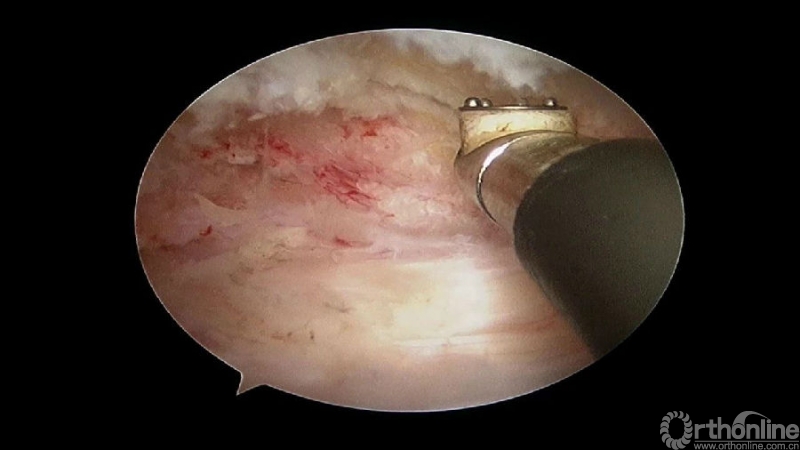

手术步骤:

1.骨赘位于左侧,选择右侧入路做C4/5椎板切除减压;

2.显露骨赘的内侧面及上下缘;

3.从游离骨块的背侧开始,用磨钻将骨块打薄,然后将骨块的底面与脊髓表面仔细分离,将游离骨块摘除;